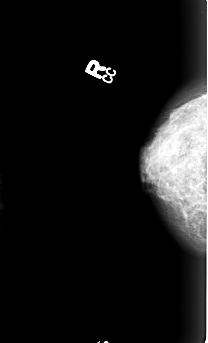

B_3005_1.RIGHT_CC

RIGHT_CC LINES 4456 PIXELS_PER_LINE 2696 BITS_PER_PIXEL 12 RESOLUTION 50 NON_OVERLAY

FILE: B_3005_1.LEFT_CC.OVERLAY

TOTAL_ABNORMALITIES 1

ABNORMALITY 1

LESION_TYPE CALCIFICATION TYPE PUNCTATE-AMORPHOUS-PLEOMORPHIC DISTRIBUTION CLUSTERED

ASSESSMENT 4

SUBTLETY 3

PATHOLOGY MALIGNANT

TOTAL_OUTLINES 1

BOUNDARY